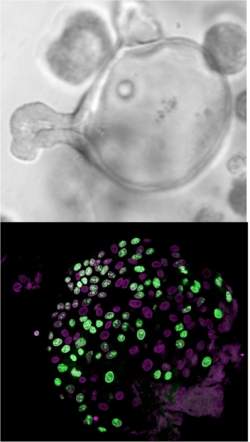

As células-tronco intestinais geram organoides esféricos quando são cultivadas em laboratório (em cima). Sob o microscópio (embaixo), esses organoides revelam sua composição, basicamente células não diferenciadas ou proliferativas, as células do intestino.

Cientistas da Universidade de Barcelona, na Espanha, conseguiram pela primeira vez identificar e cultivar em laboratório células-tronco intestinais.

A descoberta dá aos cientistas uma "receita" precisa para isolar as células-tronco do cólon e derivar delas linhagens que podem crescer sem se diferenciar por meses.

"De fato, nós já conseguimos manter as células tronco em um disco de Petri por até 5 meses, ou podemos induzir essas células a se diferenciarem artificialmente, como acontece com elas no interior dos nossos corpos," diz o pesquisador.

Como as células-tronco intestinais regeneram nosso intestino continuamente, os cientistas acreditam que o avanço terá grande impacto sobre a chamada medicina regenerativa, que busca formas de desenvolver novos tecidos, e até novos órgãos, para repor os que se degeneram com o tempo ou por doenças.